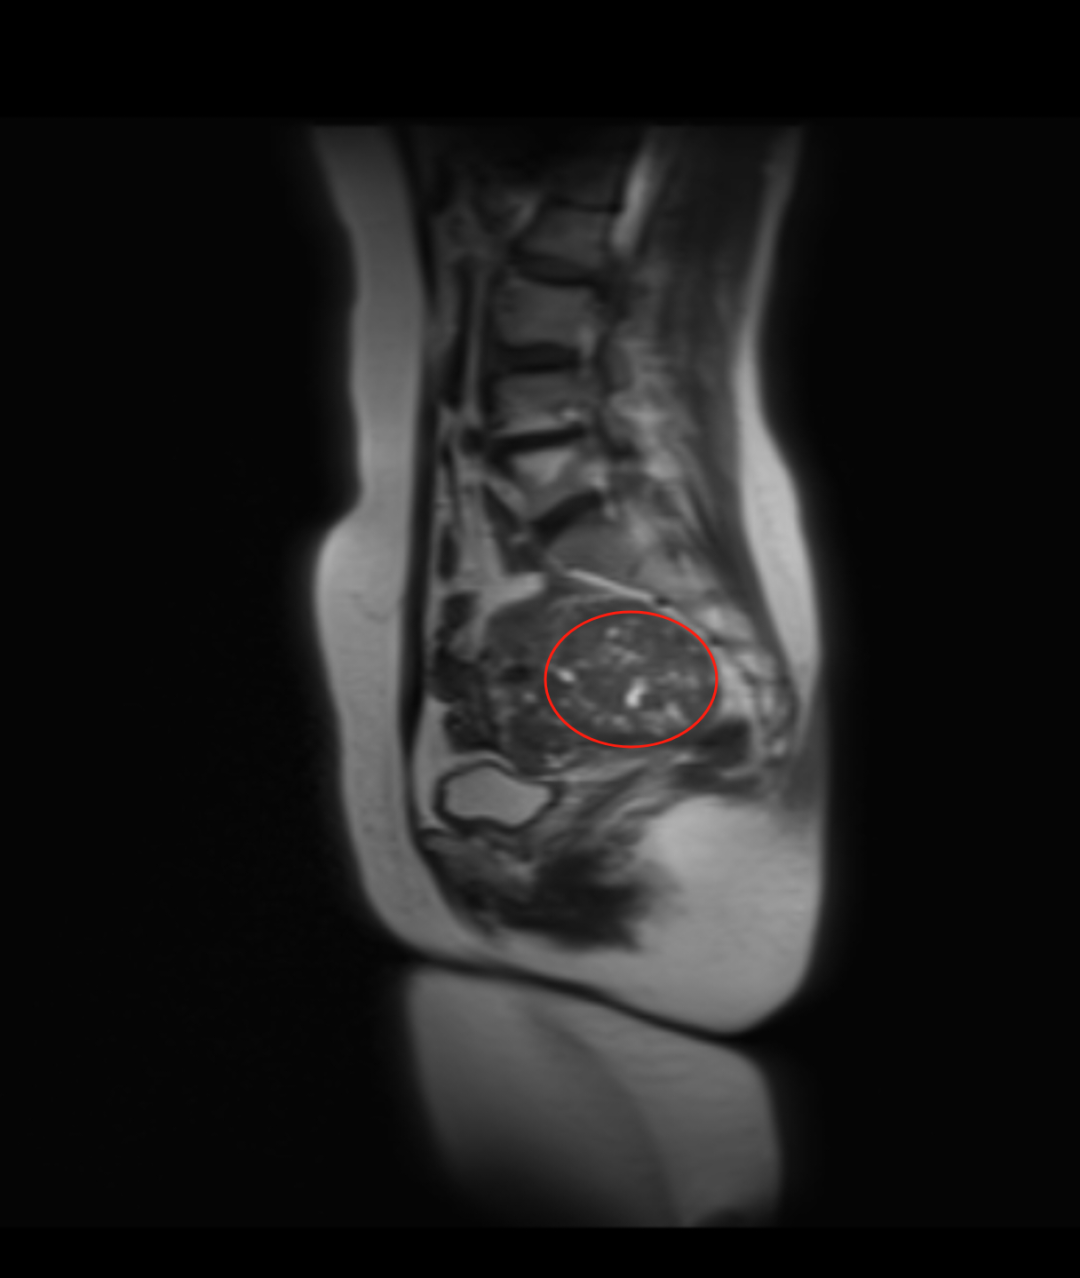

入院后,妇科团队为戴阿姨完善了盆腔增强MRI、肿瘤标志物、性激素六项等相关检查。结合影像学特征和实验室结果,初步诊断为“子宫阔韧带良性肌瘤”。徐彩临院长带领妇科医护团队立即展开病例讨论:患者53岁,处于围绝经期,肌瘤体积较大(直径超10cm),虽考虑良性,但已可能压迫周围脏器,且存在潜在生长风险,符合手术指征。腹腔镜微创手术具有切口小、出血少、术后恢复快等优势,最终确定腹腔镜下右侧阔韧带肌瘤剔除术为首选方案,但手术难度大。